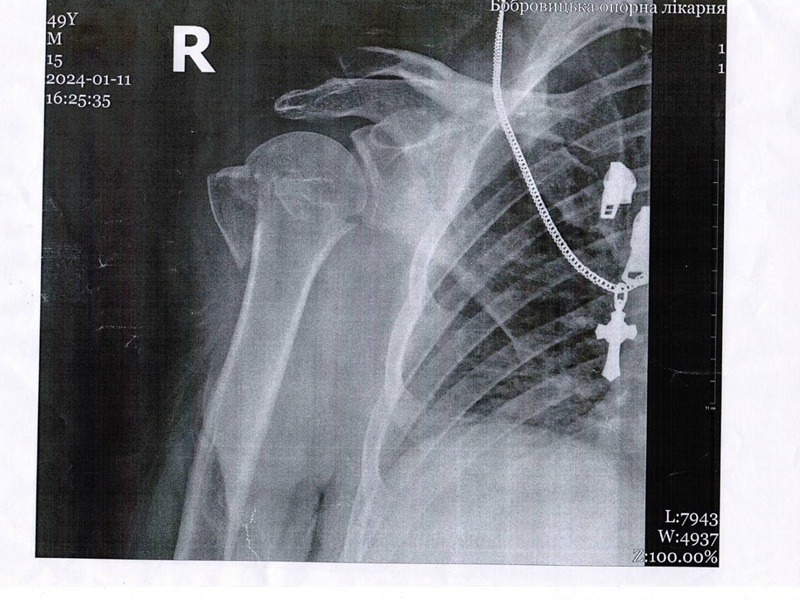

Остеосинтез плеча вивих ДО-ПІСЛЯ: